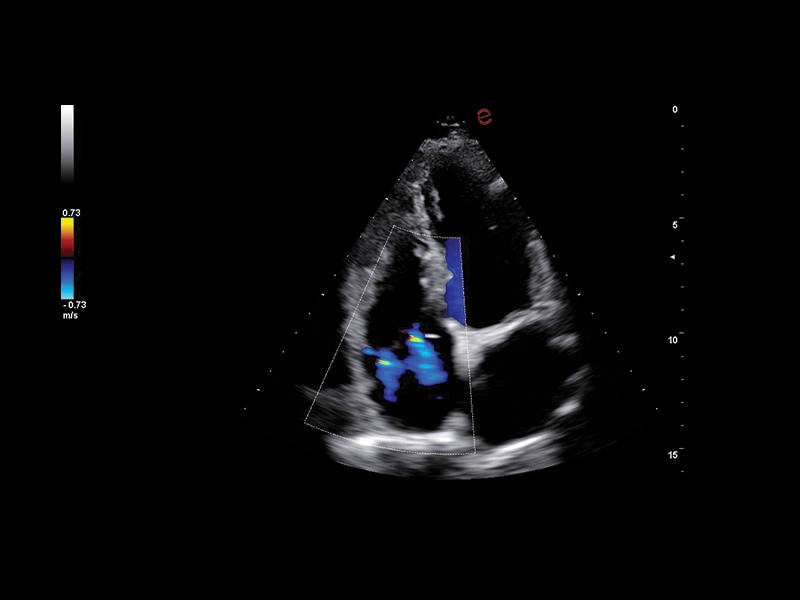

MyLab™C30 - CFM - TR

MyLab™C30 - CFM - TR